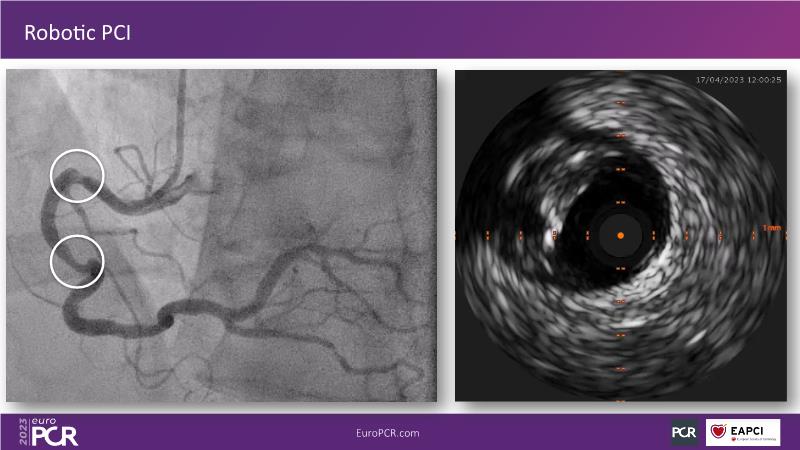

Robotic PCI: real-life experience with a new robotic platform

The current problems in interventional cardiology have been the same for years: exposure to X-rays, or orthopaedic injuries to operators after decades in the cathlab. The solution to these problems could lie in robotics and the increasing use of artificial intelligence in practice. Follow this session on the future of robotics to learn more about the benefits it could bring.

- To understand the concept and benefits of robotic PCI with the R-One system